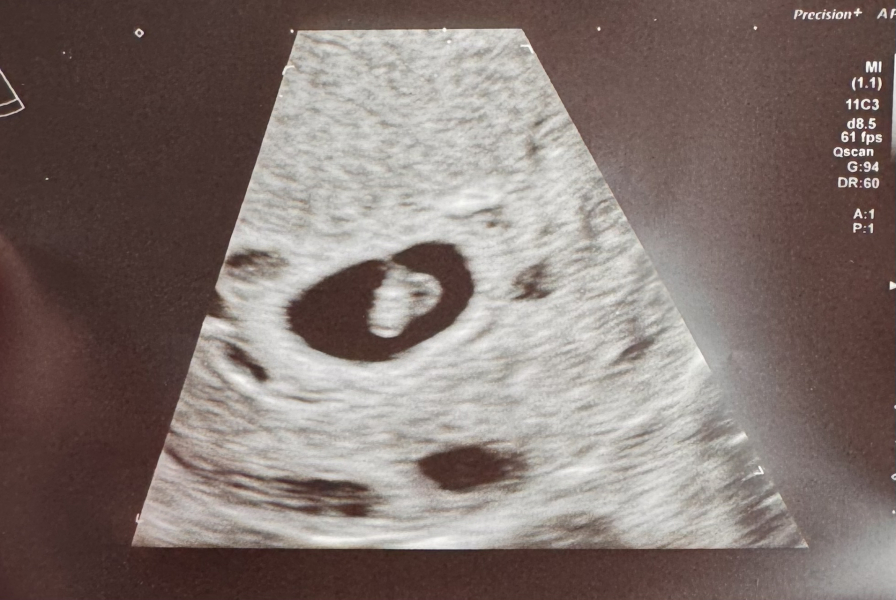

californiacooper · 08/02/2024 12:00

I've got home from EPU... I was so nervous today. It was really make or break if it hadn't developed.... but... I have a tiny tiny bean with a tiny flickering heart ❤️😭❤️. It's only measuring 6+0 (and was 5+0 last Tuesday, and based on my LMP which was 20 december I thought it would be 7.... but.... I need to not worry about that as I think it's good news for the minute!)

No date yet but I'll probably be due in October though but I'm not sure I can leave you September guys!

@californiacooper I am so pleased you’ve had a positive scan and you got a little heartbeat as well!

Omg yayyyy!!! After everything you’ve been through as well, being told nothing was there and now look at that scan! That’s brilliant news ❤️‍🔥❤️‍🔥❤️‍🔥